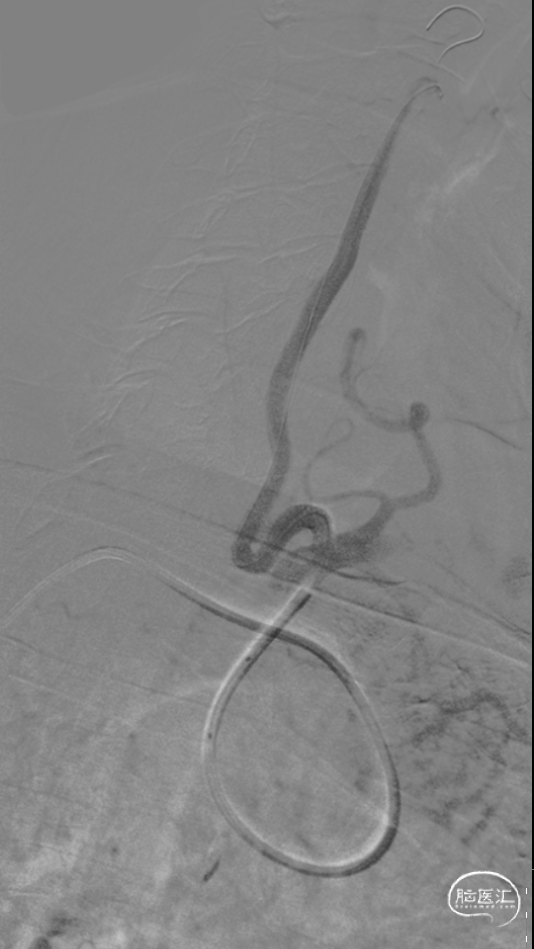

5

经过测量后,选择4.0mm*13mm Bridge椎动脉雷帕霉素靶向洗脱支架,沿微导丝将支架输送至狭窄处,造影确认位置良好,缓慢充盈至10atm,30s后泄压,造影见支架定位良好,残余狭窄约为40%,再次送入球囊扩张,10atm缓慢充盈,30s后泄压,造影见支架定位良好,贴壁良好,前向血流较前改善,无残余狭窄。